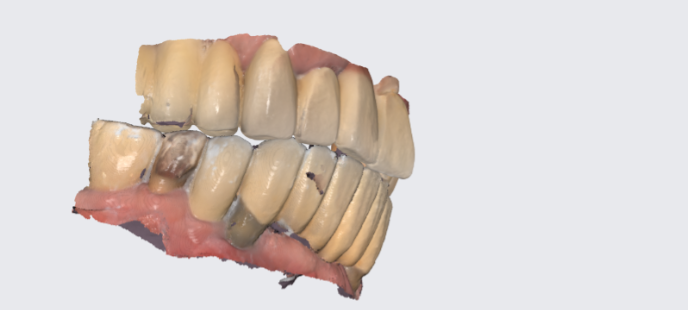

치아의 대부분을 임플란트로 교체하였어도

매번 수술을 앞두고 긴장이 될 수도 있습니다.